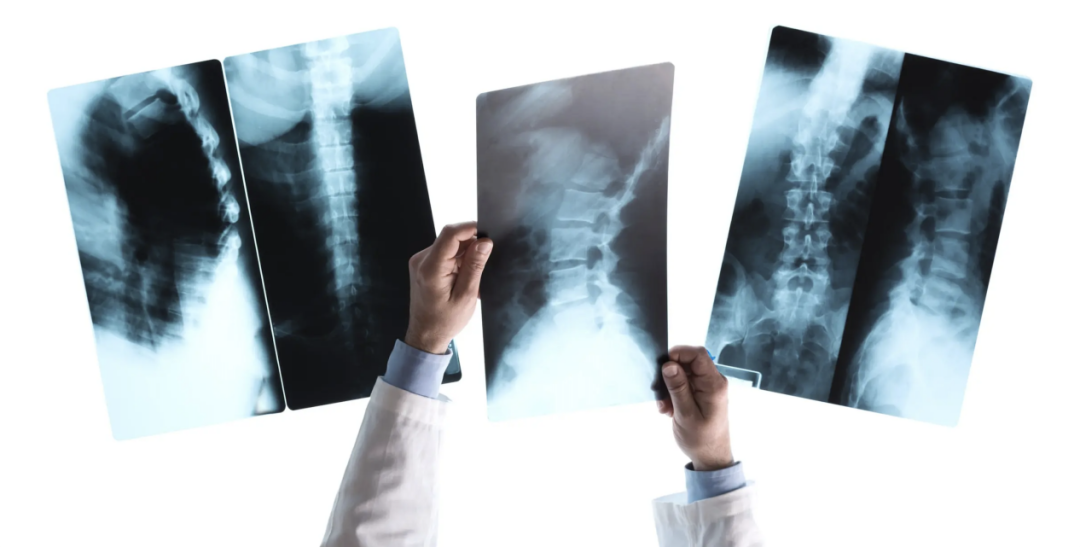

胃肠机的主要组成部分有高压发生器、球管、影像增强器、电动检查床、曝光控制台和数字处理工作站。高压发生器是用来产生X线的电源,球管是用来发射X线的装置,影像增强器是用来将X线转换为可见光的装置,电动检查床是用来调整患者的姿势和位置的装置,曝光控制台是用来控制X线的输出和曝光时间的装置,数字处理工作站是用来对X线图像进行数字化处理和存储的装置。

当患者需要进行胃肠机检查时,首先要按照医嘱做好胃肠道的准备,如空腹、服用泻药、灌肠等,以清空胃肠道的内容物,保证影像的清晰度。然后,患者要穿上专用的检查服,脱去身上的金属物品,如首饰、眼镜、牙套等,以免影响X线的穿透和图像的质量。接着,患者要根据检查的部位,采取适当的姿势,如平卧、侧卧、俯卧、站立等,躺在电动检查床上,医生会根据需要调整检查床的高度和角度,使患者的胃肠道与球管和影像增强器保持一定的距离和位置。然后,医生会让患者口服或灌入造影剂,造影剂是一种含有钡或碘的液体,它可以在X线下显示出胃肠道的轮廓和结构。

接着,医生会在曝光控制台上控制X线的输出和曝光时间,通过影像增强器X线转换为可见光,再通过电荷耦合器摄像头将可见光转换为视频信号,传送到监视器上显示,同时对视频信号进行数字化处理,实现实时的透视和点片,即可在屏幕上观察到胃肠道的形态和功能。医生会根据患者的反应和图像的变化,及时调整X线的参数和检查床的位置,使患者的胃肠道在不同的角度和方向上得到充分的显示和观察。如果需要,医生还可以通过内镜等器械,在胃肠机的指导下,进行一些治疗性的操作,如取出异物、止血、置入支架等。检查结束后,医生会对X线图像进行分析和诊断,给出相应的报告和建议。